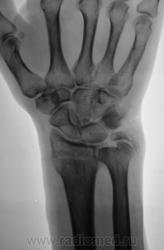

Пациент направлен на рентгенографию лучезапястного сустава.

Пациент направлен на рентгенографию лучезапястного сустава хирургом, была травма. После производства снимков стали допытываться у пациента, о "факте более ранней травмы". Все бесполезно - не помнит, не знает ....

Ваше мнение, уважаемые коллеги?